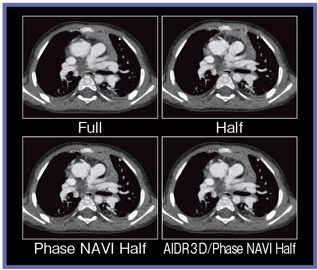

当院の井野賢司技師らは小児検査での画質向上を図るため,ボリュームスキャンに心電同期ハーフ再構成を併用する検査法を研究している。通常のヘリカルスキャンでは,心臓の動きや呼吸によるバンディングアーチファクトが生じるが,Aquilion ONEでは,ボリュームスキャンとハーフ再構成を組み合わせることで,ブレの少ない画像が得られる。ただし,これだけでは運悪く心拍動や呼吸運動の激しい時間帯が含まれてしまい,うまくいかない場合もある。そこで,任意位相を選択して再構成するために,心電計をデモモードにして心電同期スキャンを行い,ブレの少ない画像を選択することができる。これにより,被ばくを増やすことなく高画質化が可能となるが,ハーフ再構成によるノイズの増加というデメリットもある。これを改善するために,AIDR 3Dを併用することで,ノイズを抑えた高画質画像が得ることができる(図4)。

![]() 図4 ハーフ再構成とPhase NAVI,AIDR 3Dによる ボリュームスキャンの画質比較 |